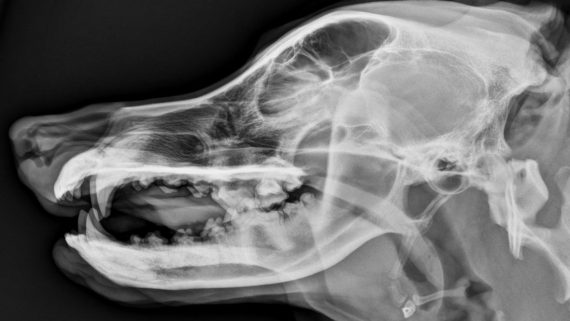

¿Os hay gustado ❤? Podéis comentar en este post! … Aunque seguro que sabréis qué animal es este último de aquí abajo